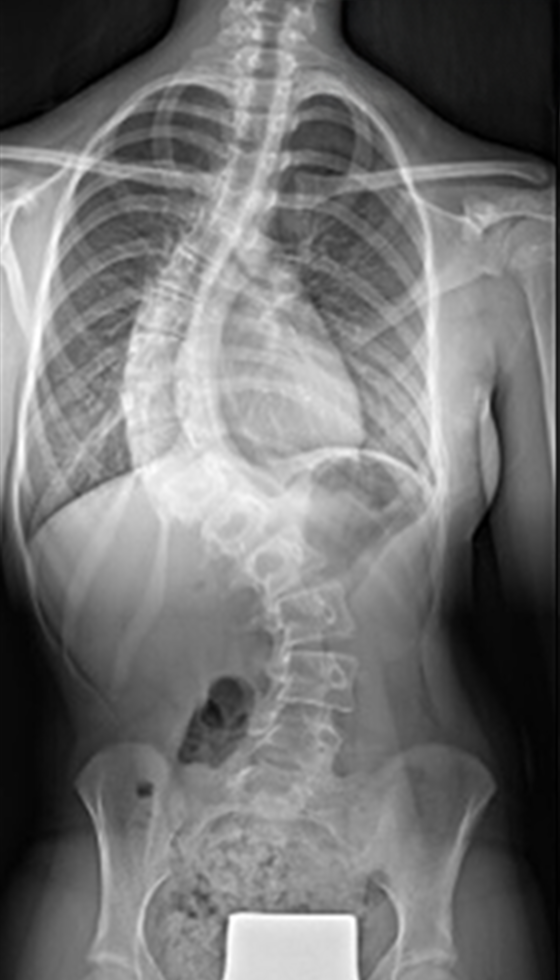

Gallery : Before - After